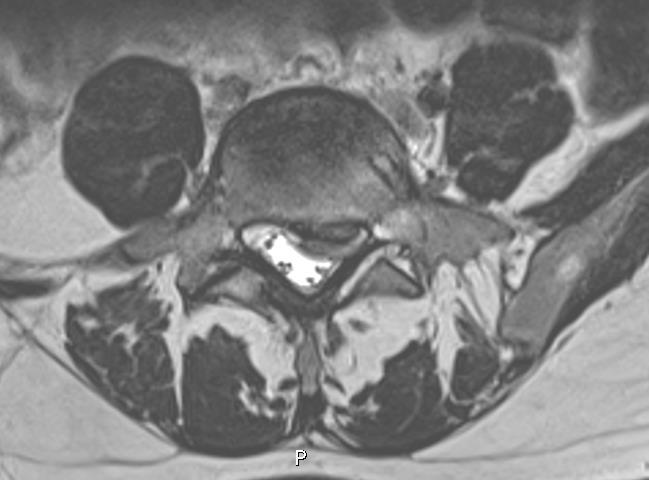

Do charakterystycznych objawów patologii widocznej na poniższych obrazach tomografii rezonansu magnetycznego należą: 1) ból okolicy lędźwiowej; 2) ból promieniujący do kończyny dolnej wzdłuż bocznej powierzchni uda, tylnej powierzchni podudzia i pięty; 3) osłabienie czucia powierzchniowego dotyku w okolicy spoidła I i II palca stopy; 4) osłabienie siły zgięcia grzbietowego stopy; 5) osłabienie siły zgięcia podeszwowego stopy. Prawidłowa odpowiedź to: